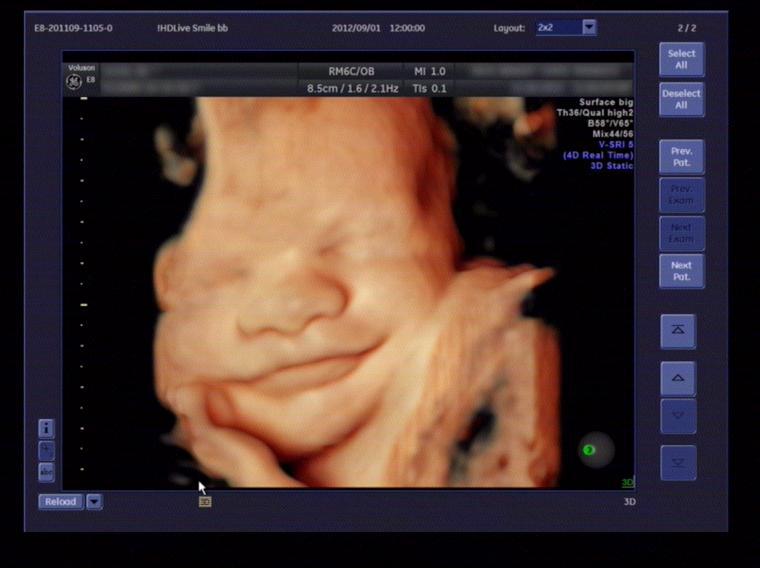

四維與三維彩超的區(qū)別:四維彩超也稱為實(shí)時三維彩超,三維彩超是靜態(tài)的,只能是某個時間點(diǎn)上的照片,四維彩超是動態(tài)的,就是在三維圖像上加上時間軸,顯示隨著時間變化而變化的立體圖像,能夠顯示未出生的寶寶的實(shí)時動態(tài)活動圖像,如打哈欠、伸懶腰、吮手指等等奇妙的動作,所以四維看起來會更清楚明晰。